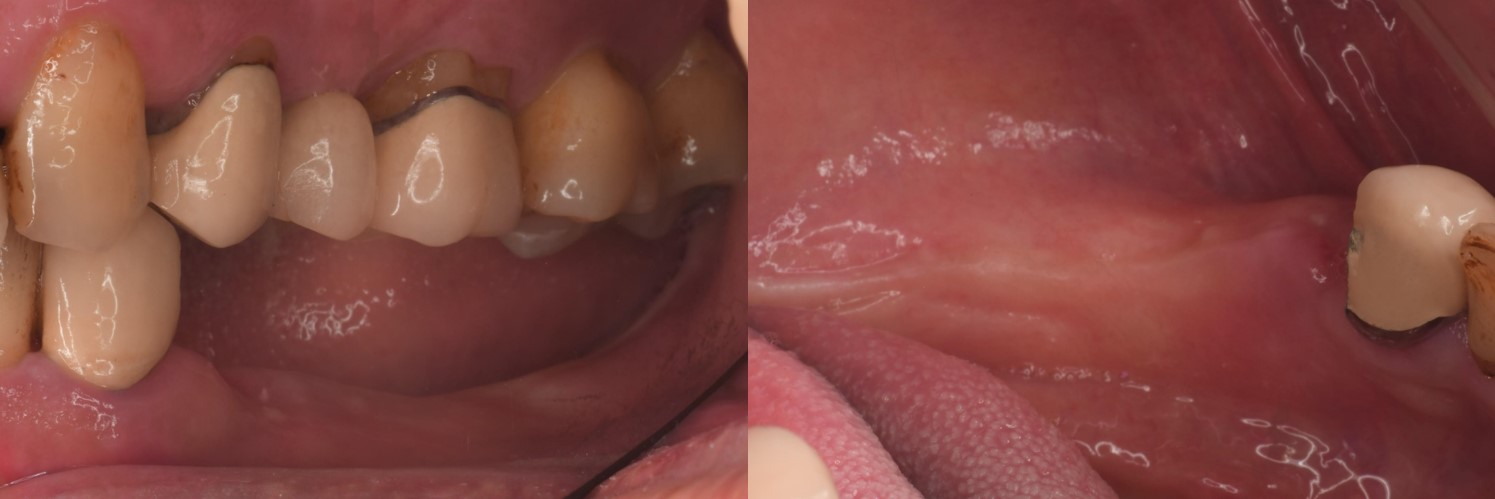

▲(治療前,左下顎缺牙,咬合喪失)

治療前,左下顎缺牙,咬合喪失

治療前,左下骨高度足夠

治療後,口內照